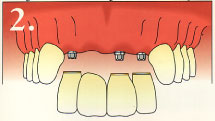

Here is an example of a single dental implant, where there are other missing teeth.

This is an example of multiple dental implants.